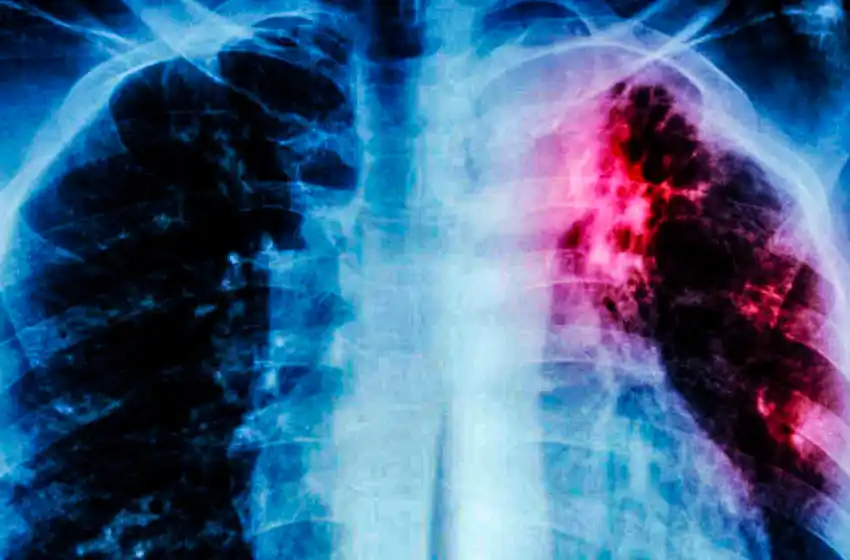

Un caso de tuberculosis fue detectado en un colegio de Mar del Plata. Esta enfermedad infecciosa de transmisión por contacto afecta principalmente a las vías respiratorias, pero puede manifestarse en otras partes del cuerpo.

Respecto a la tuberculosis explicó que "es una enfermedad infectocontagiosa que nunca ha dejado de existir, desde hace muchísimos años está, todos los conocemos que en este momento tiene tratamiento y cura. Puede ser una enfermedad pulmonar, que es la que contagia o otras formas en distintas partes del cuerpo que no contagian. Nosotros nos avocamos principalmente a la que contagia porque lo que hacemos es el estudio de contacto y la prevención".